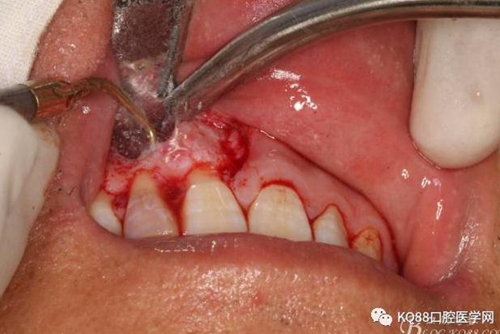

圖6.行唇側(cè)角形切口(11近中垂直切口+齦溝內(nèi)水平切口)垂直切口距離前庭溝約1~2mm。這樣可以減輕術(shù)后腫脹。

圖7. 角形切口中的齦溝內(nèi)切口情況:11號刀片伸進齦溝內(nèi)斜切。